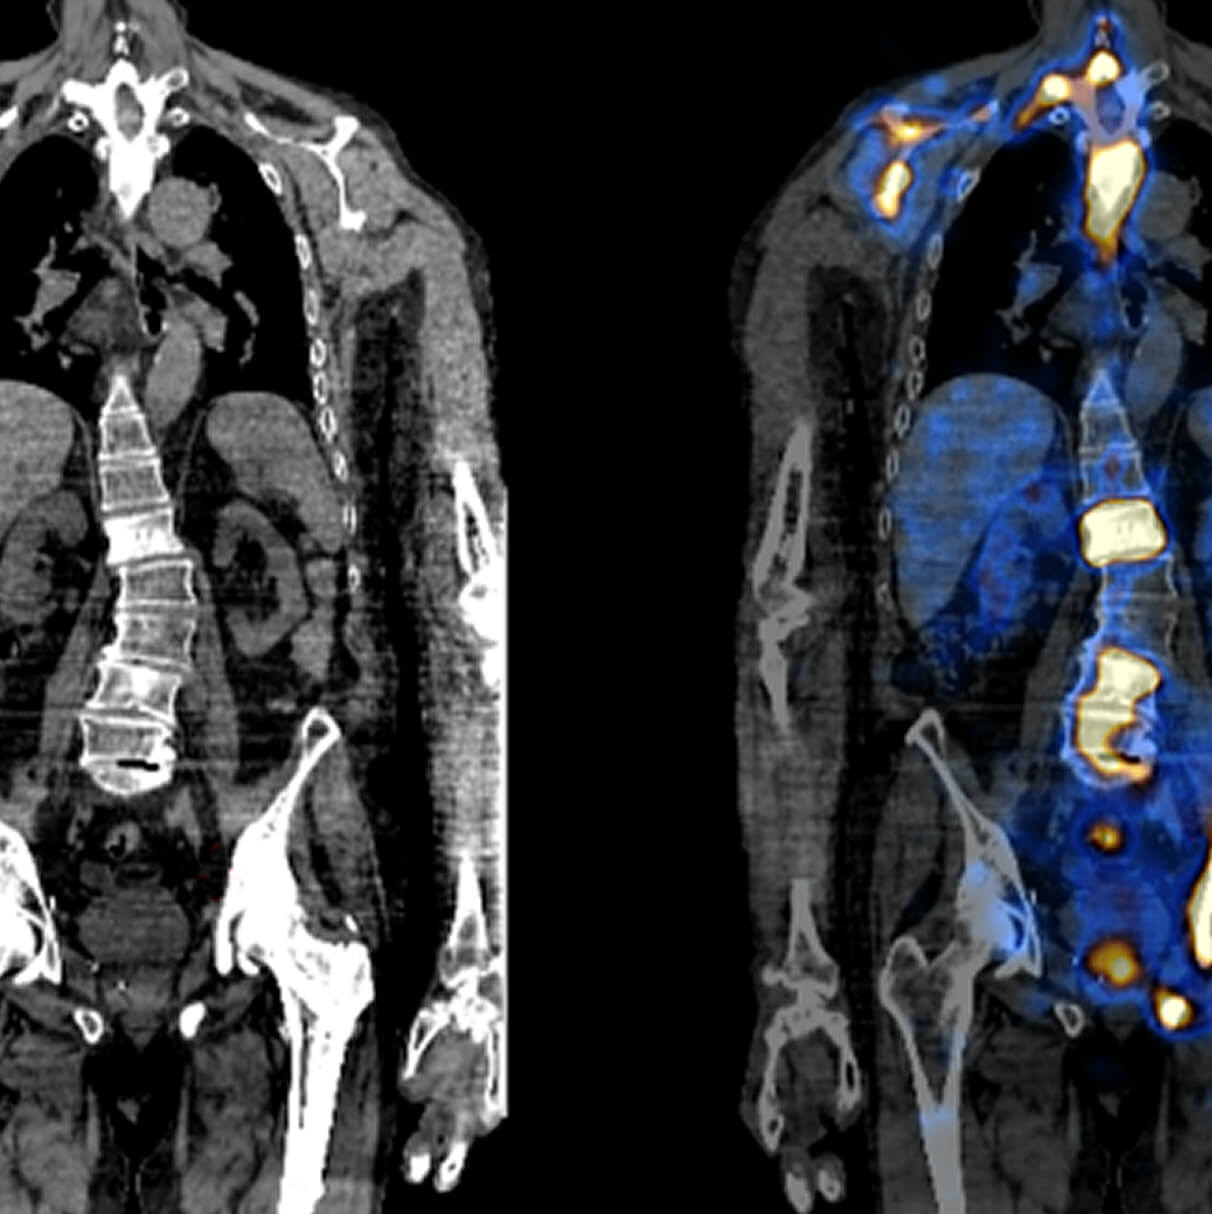

There is a world outside the stent mesh

Caso condiviso da Saima Mushtaq

Paziente con anamnesi di malattia coronarica e pregresso impianto di stent sulla discendente anteriore sinistra.

Per prima cosa, esamina l'intera scansione. Concentrati sul tronco comune e sulla porzione prossimale della discendente anteriore sinistra.